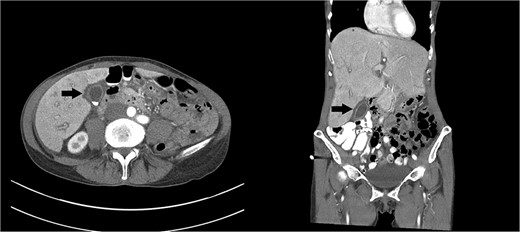

Right upper quadrant ultrasound revealed a distended gallbladder with multiple small calculi but no wall thickening nor pericholecystic fluid (Fig. 1). Intra- and extra-hepatic biliary ducts and the common bile duct were not dilated. A sonographic Murphy sign was not elicited. Computed tomography of her abdomen and pelvis revealed moderate hepatomegaly with heterogeneous enhancement, prominent hepatic veins, periportal edema and pericholecystic fluid (Fig. 2).

Axial and coronal images of a computed tomography showing a gallbladder (arrows) with multiple gallstones and pericholecystic fluid. Moderate hepatomegaly with heterogeneous enhancement and prominent hepatic veins are also present.